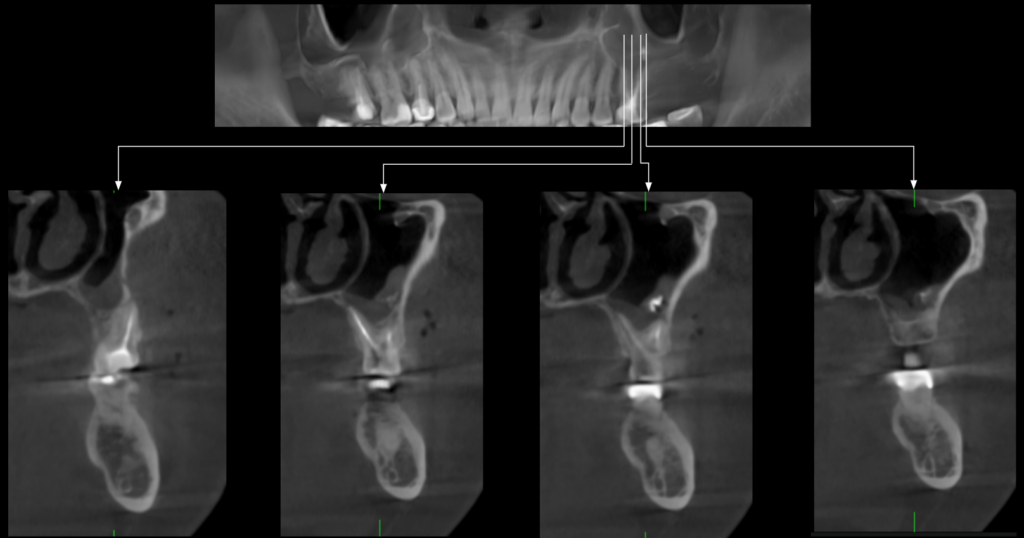

Paciente masculino de 45 años acude para una evaluación general. A la evaluación de la radiografía panorámica (Figura 1) se observa engrosamiento de la mucosa de seno maxilar izquierdo además de una imagen radiopaca proyectada en seno maxilar izquierdo; así mismo en pieza 26 se observa restauración coronaria, sellado cameral y obturación de conductos. A la evaluación de la tomografía volumétrica (cone beam) bimaxilar en los cortes axiales (Figura 2), coronales (Figura 3) y transaxiales (Figura 4) se observa que la pieza 26 presenta obturación de conductos además del engrosamiento de seno maxilar izquierdo e imagen hiperdensa de alta densidad, de

forma irregular, localizada en la mucosa de seno maxilar izquierdo.

CORTES TRANSAXIALES